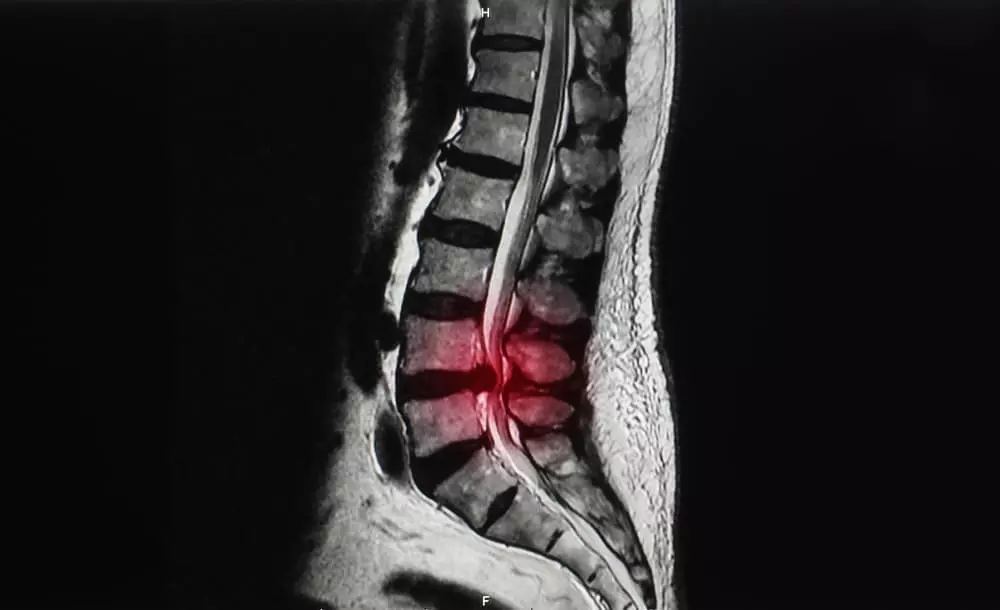

脊柱管狭窄症の治療実績

Before

After